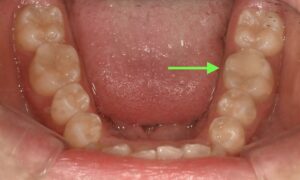

矢印の部分の歯が痛いようです。

矢印の部分が当院で治療した詰め物です。

機能させるように形を作ると、自然と他の歯と形が似てきます。